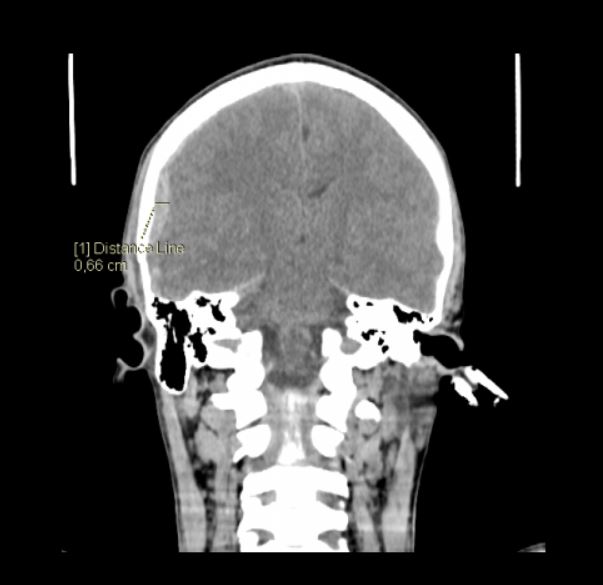

The increasing popularity of electric scooters in Poland is associated with the growing number of e-scooter-related accidents, which often involve head traumas. Although the most common types of injuries are abrasions and cuts to the skin, they sometimes include severe brain injuries. Most e-scooter accidents occur in the warm months. In winter, when there are unfavorable conditions for using this means of transport, e-scooter-related accidents are rare. Described in the text are 2 cases of severe cases of skull and brain injuries which required neurosurgical intervention. In both cases, the riders were under the influence of alcohol and did not use helmets, which had a measurable influence on the profile and the extent of injuries.